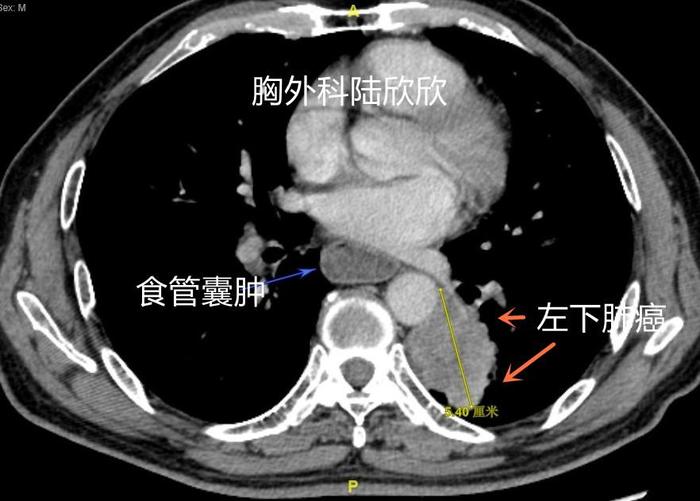

上图,两个橙色箭头指示的是左下肺的较大肺癌。可见肿瘤边缘呈现波浪状边缘。肿瘤最大径测量约55毫米。真实的肿瘤大小, PET-CT上,如果扣除瘤旁的肺炎,最大径直径小一些,大约45毫米。注意,在心脏后面、脊柱前面食管扩张明显,直径约3厘米,薄层CT可见食管上下壁的厚度一致,而且PET-CT未见食管癌征象。

上图,背段支气管后方,可见一枚转移淋巴结,术后的病理证实。